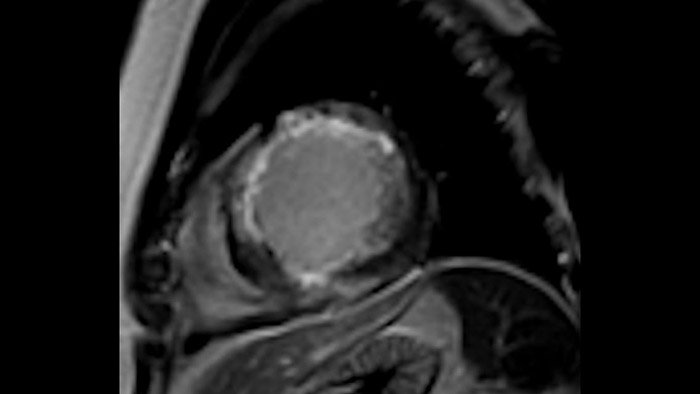

Diagnostic and prognostic utility of cardiac MR is increasing. Assess the anatomy and function of the heart using cine acquisitions, acquire information about perfusion and viability of the cardiac tissue, visualise potential edema with black blood sequence, access and even quantify tissue characterisation with CardiacQuant.